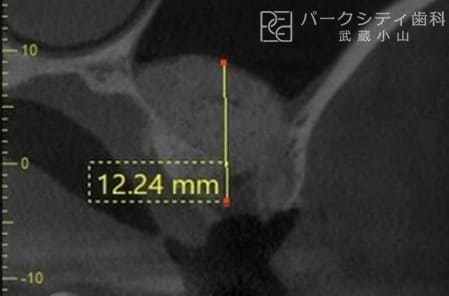

上顎洞挙上術(ラテラルアプローチ)

- 適応症:

上顎の奥歯部分の骨の高さが不足している場合。 - 方法:

上顎洞の底に人工骨を入れ、骨の高さを増やします。 - メリット:

広範囲に骨を増やすことができ、インプラントの埋入が可能になります。 - デメリット:

手術が大掛かりで、回復に時間がかかることがあります